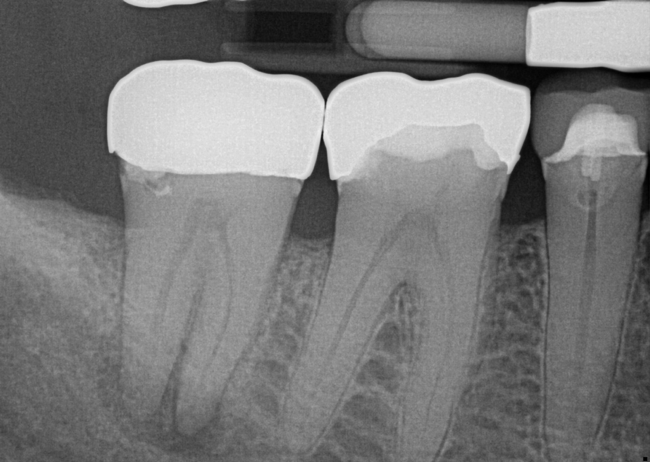

Treatment of combined endodontic and periodontal lesions does not differ from the treatment of either an endodontic lesion or a periodontal lesion. The part of the lesion sustained by the root-canal infection can usually be expected to resolve after proper endodontic treatment. Timing of the completion of the root-canal therapy, medicaments used, and assessment of restorability are considerations for the long-term success and survival of the tooth.7 Figures 7, 8, and 9 represent the timing of completion and restorative decision-making to complete all therapies.

In Figure 7, the periapical radiograph identifies the presence of the combined endodontic-periodontal lesion developing due to a carious lesion beneath an existing vintage gold crown with ill-fitting margins. Intraoral examination revealed a fistula developing and moderate pain on percussion and mastication. After occlusal access and clear visualization of the canals, the canals were shaped using the rotary files, with precautions taken not to perforate or enlarge the apical foramen. Maintaining the endodontic therapy within the canals prevents the infection from being introduced into the surrounding periodontium. In this case, calcium hydroxide medicament was placed into the canals and evaluated 30 days postoperatively.8

Fig 7. Primary endodontic and secondary periodontal lesion, mandibular second molar.

Figure 7